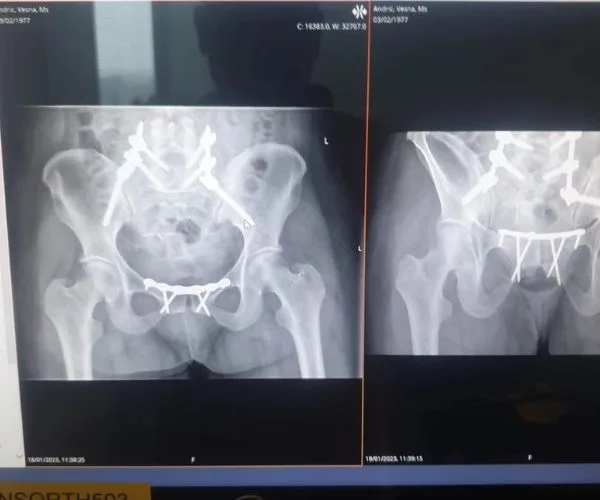

My spine had been crushed and snapped off my pelvis, I had five broken ribs, a punctured lung and a dislocated rib.

“We’ve inserted metal plates and screws to put your back together,” he said. “We’ll remove them in about six months.”

Vesna Andric x-rays